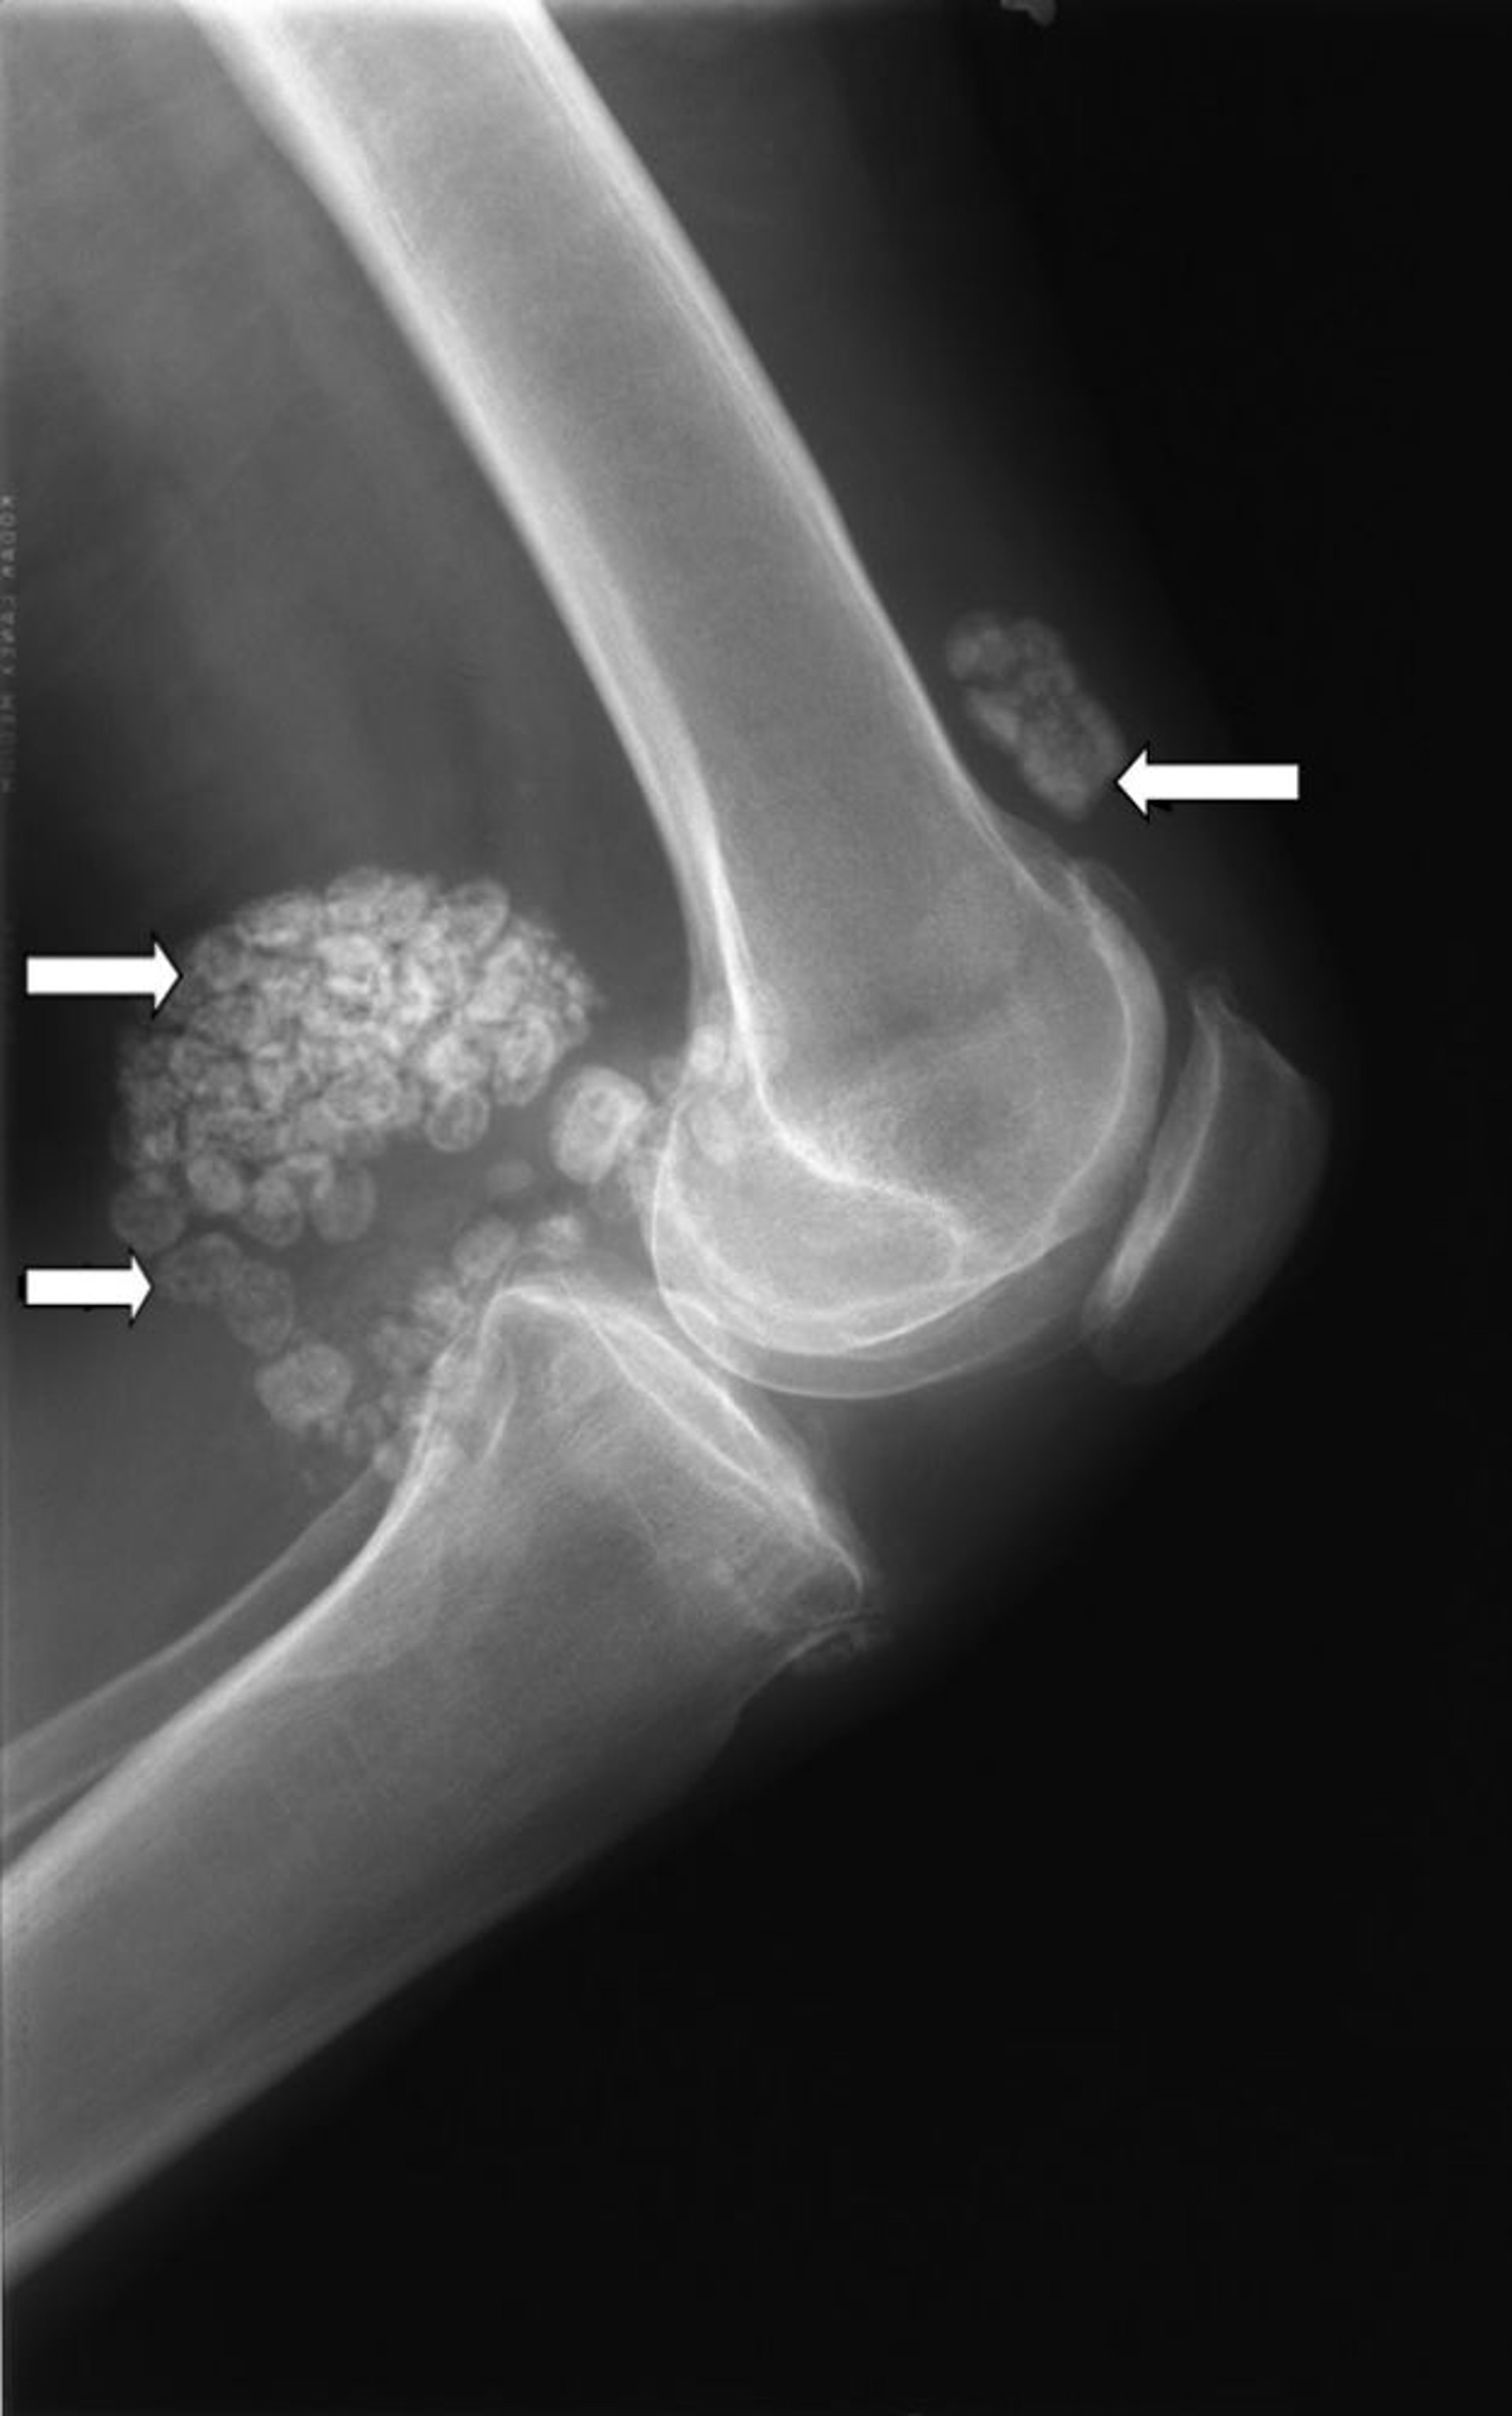

साइनोविअल कॉन्ड्रोमेटोसिस

घुटने का यह एक्स-रे साइनोविअल कॉन्ड्रोमेटोसिस नामक कार्टिलेज के एक से अधिक गुच्छों (तीर) को दिखाता है।

मिशेल जे. जॉयस, MD, और हैकन इलास्लैन MD के छवि सौजन्य से।